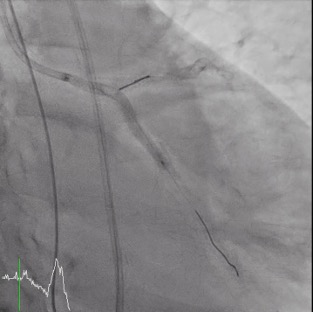

Percutaneous coronary intervention (PCI) was initiated by a right femoral approach using a 7 Fr EBU 3.5 guide catheter. We started from NC balloon and cutting balloon for lesion preparation, then first BMS was deployed successfully but the 3.5 X 48mm DES was hard to push even by side branch and distal anchor technique. We changed our strategy from 1 long stent to 2 shorter stent with a shorter DES and it work. But, due to the jailed LCX orifice, the reversed culotte technique was used with the opened 48mm DES at the beginning as bail out 2 stent strategy. We were able to deployed the opened 48mm DES at the LM-LCX successfully, however, the balloon could not be deflated and was stuck! We hurriedly tried the opened cutting balloon and back-and-forth traction but failed. Even worse, the balloon shaft snapped! We tried to engage the guiding to catch the balloon but failed again. Overall, this was a catastrophe with an un-deflated fractured balloon trapped and stuck at the left main coronary artery.The patient complained of severe chest pain accompanied by a dropping blood pressure. We administered Bosmin with Levophed pump for the shock status and contacted the Cardiovascular surgeon and ECMO team immediately. For our last resort, we tried the Snare to catch the proximal tip of the undeflated fractured balloon and finally we succeeded. We were able to capture the balloon and retrieve it, with the angiography resulted expanded stent with normal coronary flow.

Case Summary

Balloon entrapment is an uncommon complication during PCI. We can try gentle traction if deflation is possible, and advance another guide extensor for retrieval. But if the balloon fails to deflate, with balloon shaft fracture. This is even rare and one of the most dreaded complications, especially at the left main, which can occlude coronary flow, causing myocardial infraction, shock, and even death. If such an unfortunate event occur, stay calm then stabilize the hemodynamics (including vasopressor, IABP, ECMO). Several percutaneous maneuvers (ex. Snare) can be tried, and do not hesitate to contact the surgeons for emergent operation if the efforts fail.